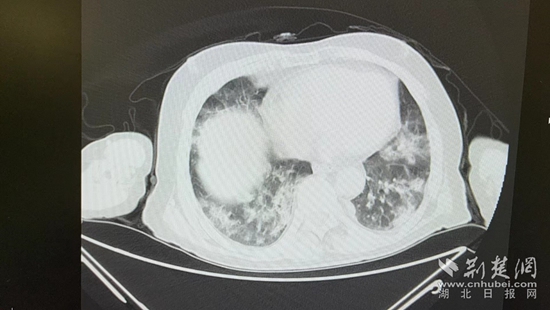

病情的突然惡化,會不會與近期的新冠病毒感染有關?雖然家屬反映,曾多次在家自測抗原正常,但徐濤還是力排眾議,說服老人進行核酸檢測和肺部CT檢查。結果顯示核酸陽性,60%白肺,結合老人的表現,這正是一例典型的老年人“沉默性肺炎”。

胸部CT片。通訊員 供圖